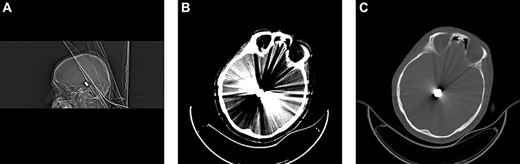

After 10 days, the patient’s neurological status worsened. Painful stimuli elicited purposeful movements of the right arm and leg. However, further examination revealed left hemiplegia with anisocoria. Emergent unenhanced head CT revealed the spontaneous migration of the bullet from the posterosuperior side of the mesencephalon to the occipital region on the left side (Fig. 2). Moreover, hydrocephalus improved. The patient’s cerebrospinal fluid was thoroughly examined for the presence of bacteria. However, the cerebrospinal fluid was sterile. Surgery was performed immediately on the ventriculoperitoneal shunt to treat hydrocephalus. On the third day after surgery, the patient could follow simple commands and showed increasingly purposeful movement on the right side. However, left hemiplegia and anisocoria did not improve. The bullet appeared removable. Therefore, we decided to remove the migrating bullet after the patient’s neurological status improved.

Follow-up CT after 10 days of admission revealed inferior and retrograde migration of the bullet to the left cerebellar peduncle. (A) Sagittal bone window. (B) Brain. (C) Axial bone window. (D) Postshunt operation control. Sagittal bone window. Ventricular catheter is observed.